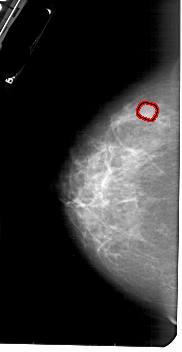

FILE: A_1838_1.LEFT_CC.OVERLAY

TOTAL_ABNORMALITIES 1

ABNORMALITY 1

LESION_TYPE MASS SHAPE LOBULATED MARGINS OBSCURED

ASSESSMENT 3

SUBTLETY 4

PATHOLOGY BENIGN

TOTAL_OUTLINES 1

BOUNDARY

LEFT_CC LINES 5266 PIXELS_PER_LINE 2716 BITS_PER_PIXEL 12 RESOLUTION 43.5 OVERLAY